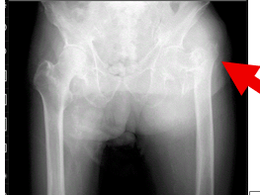

【在宅でみる大腿骨近位部骨折】手術できない高齢者をどう支えるか

高齢化の進行に伴い、大腿骨近位部骨折(だいたいこつきんいぶこっせつ)を受傷される高齢者が年々増加しています。 通常であれば手術が推奨される骨折ですが、 全身状態が悪い すでに歩行困難 認知症が進行し、手術後の脱臼肢位保持が難しい といった理由から、「 手術適応なし...

5月19日読了時間: 3分